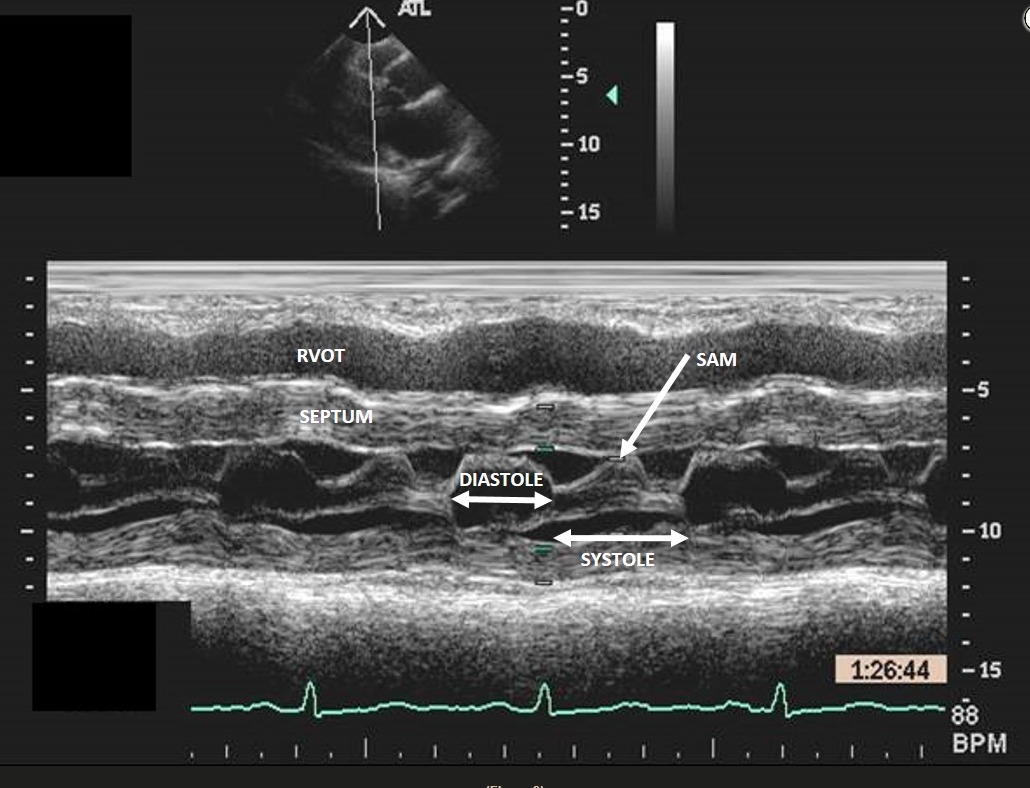

Early septic shock is often characterized by hypovolemia, reduced left ventricular afterload, and increased inotropy, conditions that favor intraventricular flow obstruction (IVO). Left ventricular hypertrophy may contribute, especially in patients with hypertrophic obstructive cardiomyopathy (HOCM), but IVO is seen in roughly 20% of all patients in early sepsis. Dynamic obstruction is usually localized to the left ventricular outflow tract (LVOT) and due to systolic anterior motion of the mitral valve as flow acceleration tends to draw the anterior leaflet into the LVOT (Bernoulli effect). IVO is sometimes seen in the midventricle, particularly in association with takotsubo cardiomyopathy. In this case, M-mode imaging across the mitral valve shows normal valve opening during diastole but abnormal anterior motion of the anterior mitral leaflet during systole, or systolic anterior motion (SAM) (Figure 3). For comparison, both mitral leaflets should remain opposed throughout systole (Figure 2, arrow). The case patient also has HOCM (interventricular septum measures 1.9 cm). Other echocardiographic findings of SAM include turbulent flow visualized as a mosaic pattern on color Doppler imaging; early systolic closure of the aortic valve and fluttering of the aortic valve leaflets; and high, late-peaking flow seen on continuous-wave Doppler imaging through the LVOT.